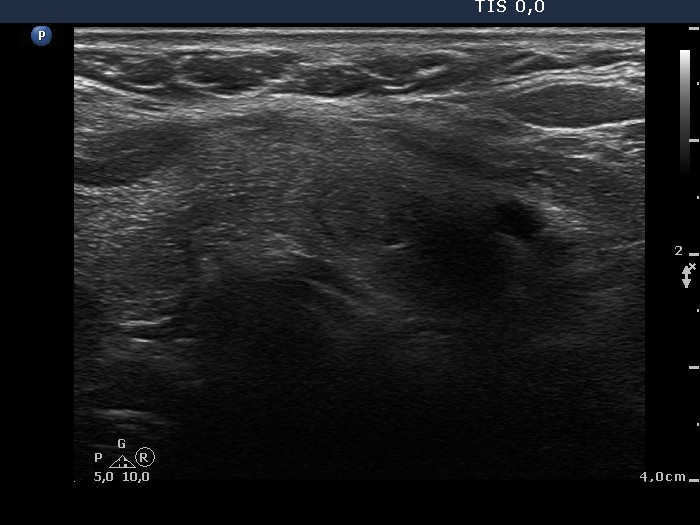

100 consecutive cases of papillary cancer - case 048 (ultrasonographic picture 7)

Lower part of the left lobe, transverse scan. There is a hypoechogenic area. The borders are blurred only because of technical reasons; I could not fit the probe all along to the neck of the patient.